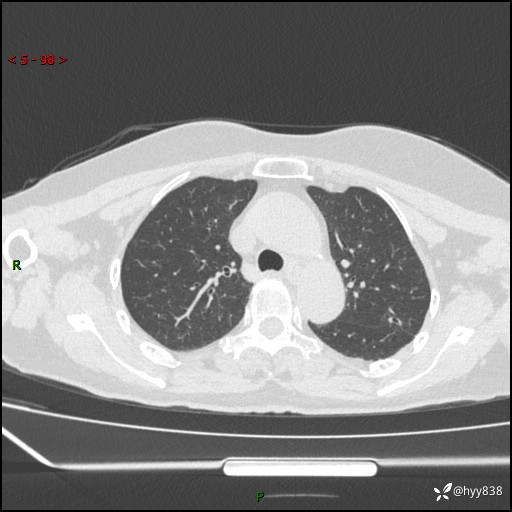

老年女性,偶然发现肺结节10天。结节不大,空洞不小,还牵拉胸膜---结果公布~

现病史:患者10余天前因“左侧鼻塞伴鼻腔异味2月”就诊于我院耳鼻喉科,查胸部CT示:左上肺结节影,建议复查。患者偶有咳嗽、咳痰,多咳白痰,无畏寒、发热,无胸痛、呼吸困难等,现为进一步明确肺结节性质,就诊于我科门诊。现以“孤立性肺结节”收住我科。 起病来,患者精神、食欲、睡眠尚可,体力、体重无明显变化。

胸部CT(2024.7.16)